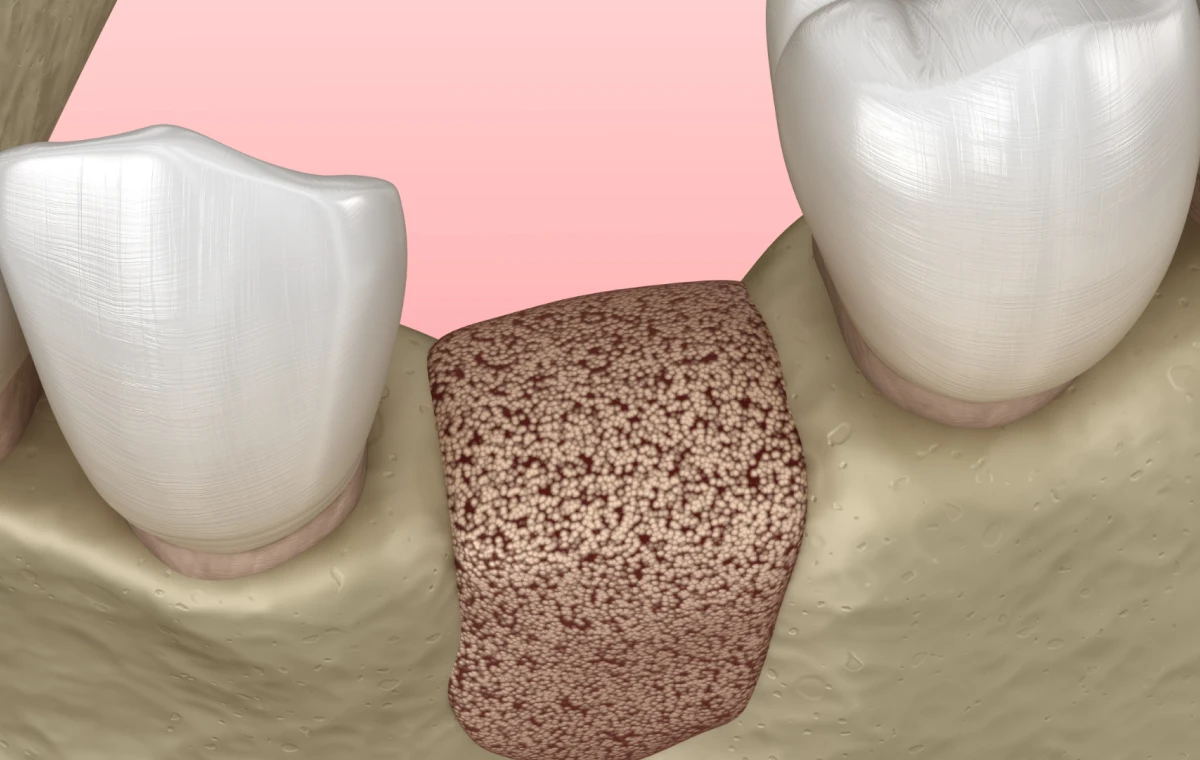

Sous anesthésie locale, une incision est pratiquée pour soulever un lambeau et exposer l’os. Après préparation, le biomatériau est placé et recouvert par une membrane.

Les matériaux de comblement

- Autogreffe : os prélevé sur le patient (mandibule, crête iliaque).

- Allogreffe : os humain issu de banques spécialisées.

- Xénogreffe : biomatériaux d’origine animale, souvent bovine.

- Biomatériaux synthétiques : hydroxyapatite, phosphates de calcium.